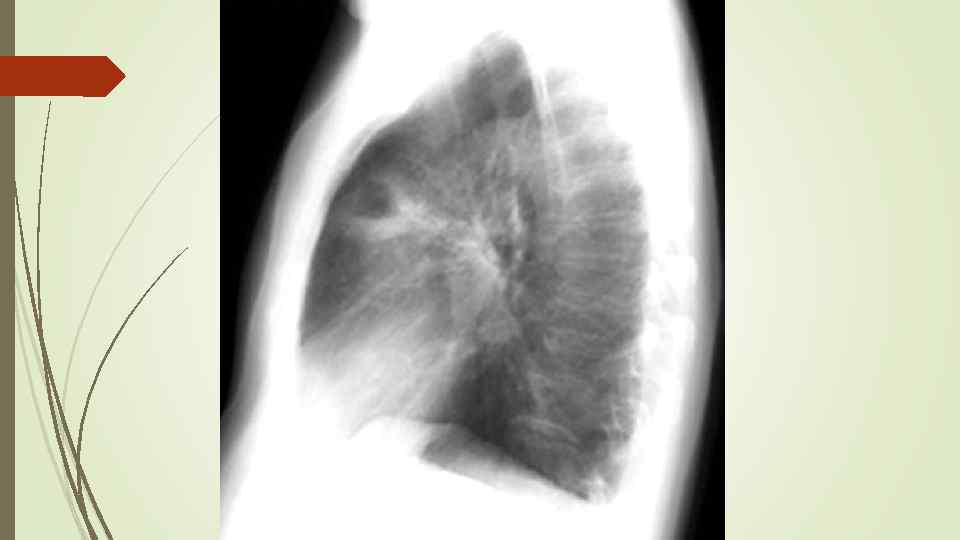

Через неделю

Через неделю

Через 5 недель

Через 5 недель